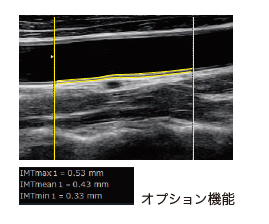

ワンタッチで自動計測 Auto IMT

・自動IMT計測